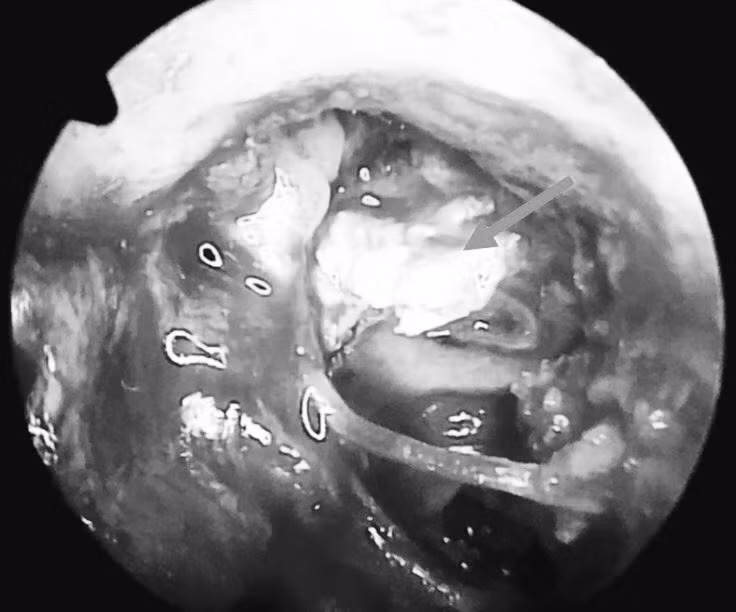

Kết quả phát hiện khối bất thường trong tai giữa lan rộng và hình ảnh mất liên tục hệ thống xương con trong tai giữa bên trái, sức nghe tai trái giảm khá nhiều nên bé chỉ nghe rõ được âm thanh bằng tai phải.

Sau 5 giờ phẫu thuật, khối cholesteatoma ăn mòn xương trong tai giữa trái đã được lấy sạch và kiểm soát tốt.